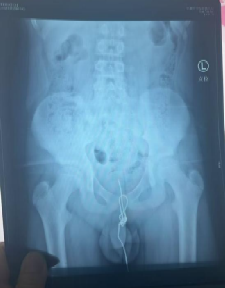

这名12岁男孩正处于对世界充满好奇的年纪,尤其对自己的身体结构满是懵懂的探索欲。某天玩耍时,他突发奇想,拿着一根较长的数据线尝试塞入尿道,可这一“试探”瞬间酿成大麻烦——数据线一端滑入膀胱,尿道球部却意外打结,往外拔被死死卡住,往膀胱推又找不到受力点,硬生生“赖”在尿道里。

孩子疼得直咧嘴,排尿时剧痛难忍还出现血尿,父母发现后立刻带他直奔医院。接诊的张林琳教授团队检查后也捏了把汗:“尿道异物本就危险,还打了结,稍有不慎就会损伤黏膜、引发感染。”

手术中,医护人员小心翼翼操作,避免对孩子娇嫩的尿道组织造成二次伤害,最终成功将数据线完整取出。看着这根让孩子遭罪的数据线,父母既心疼又懊悔:“早知道就多管管他,早该早点给他讲这些知识。”